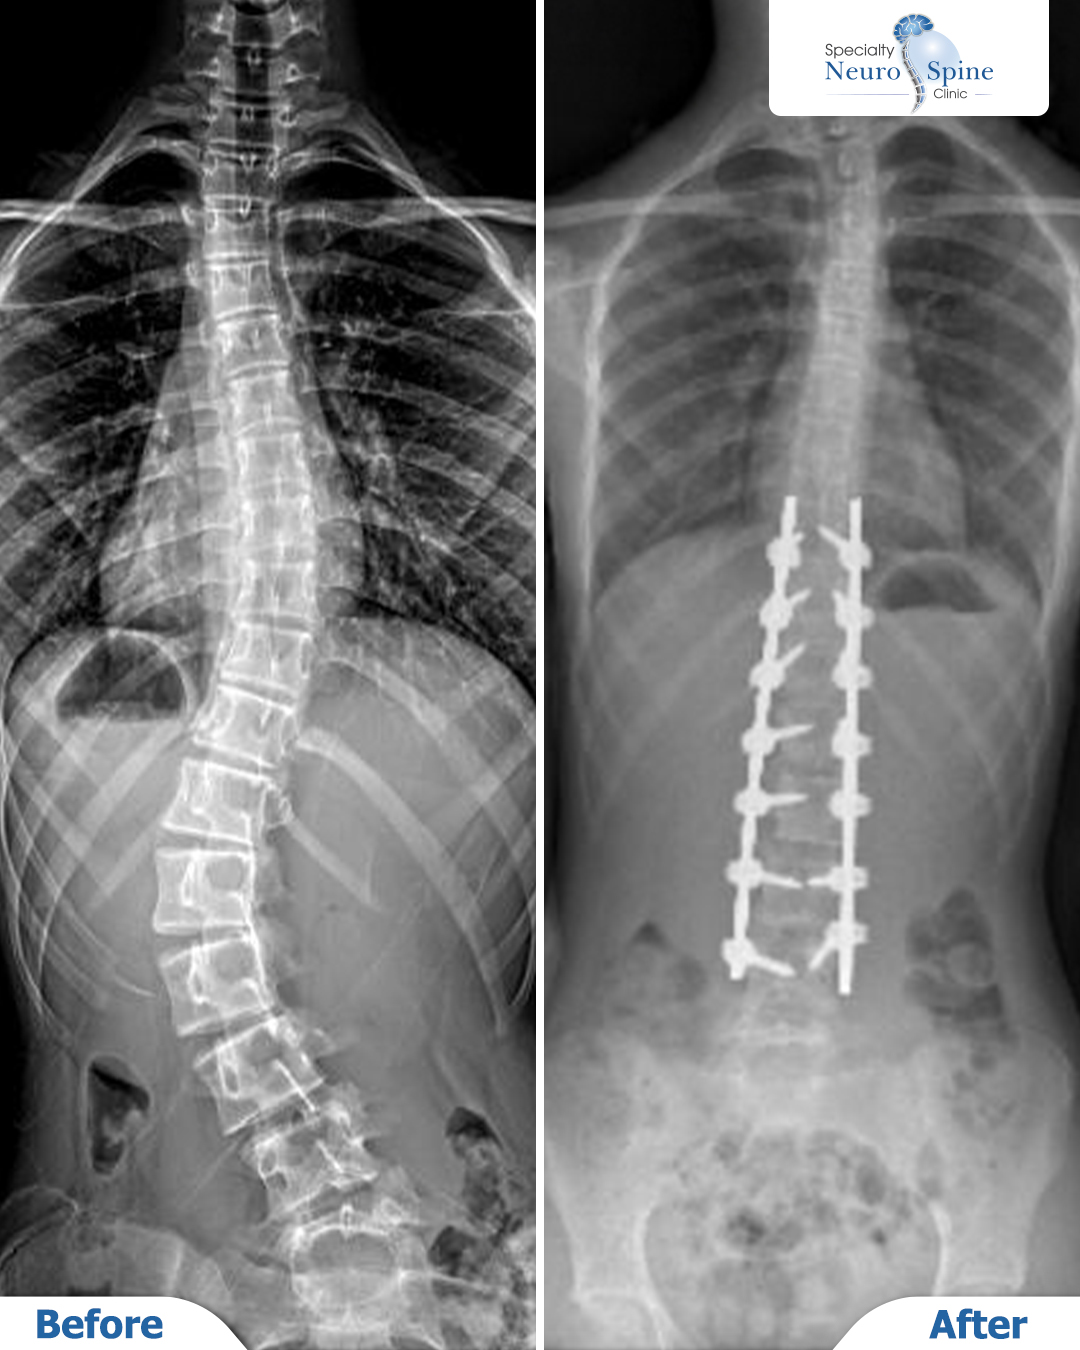

Our brave patient, Ambar (13 years old) from India, was diagnosed with scoliosis several months ago, with a curvature reaching 47 degrees.

X-ray images of our brave patient, Ambar (13 years old) from India, showing the correction of a 47-degree spinal curvature.

The surgery involved correcting the deformity from the 10th thoracic vertebra (T10) to the 4th lumbar vertebra (L4). Post-operative images demonstrate a clear straightening and a significant improvement in spinal alignment.

These precise results reflect the success of surgical planning and execution in adolescent scoliosis cases.